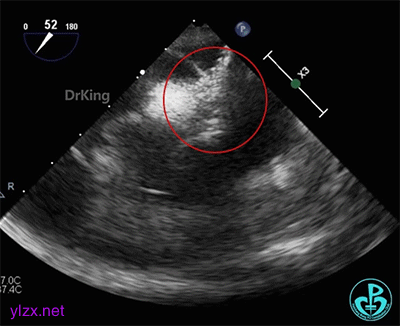

术前经食道超声描述:室间隔连续完整,房间隔中部菲薄,呈瘤样凸向右房面,基底宽约12mm,膨出约8mm。卵圆窝处薄弱,呈纤细线样回声,原发隔与继发隔间见纤细裂隙,入口约0.4mm,出口约0.8mm,卵圆瓣长约20.1mm,原发隔摆动幅度约13mm,继发隔厚约4.5mm,瓦式呼吸后,入口较宽约3.8mm,出口较宽约2.0mm,卵圆瓣左房侧末端迂曲。CDFI裂隙处可见微量左向右过隔血流信号。左心耳显示清楚,内未见异常回声。主动脉内中膜欠光滑,窦部宽约25mm,管腔未见明显狭窄与扩张,CDFI未见明显异常血流信号。各房室腔比例尚可,未见明显节段性室壁运动异常,各瓣膜形态、结构正常,启闭尚可。

超声诊断:先天性心脏病,卵圆孔未闭(长隧道型)。

右心声学造影检查:微泡造影剂经右肘正中静脉、上腔静脉进入右房,充盈良好,可见小楔形负性充盈区,患者瓦氏呼吸后见细小微气泡自裂隙处进入左房,约25~30个,一个裂隙位于卵圆孔入口处,一个位于卵圆孔出口处。

经食道超声三维、二维和右心声学造影图像: